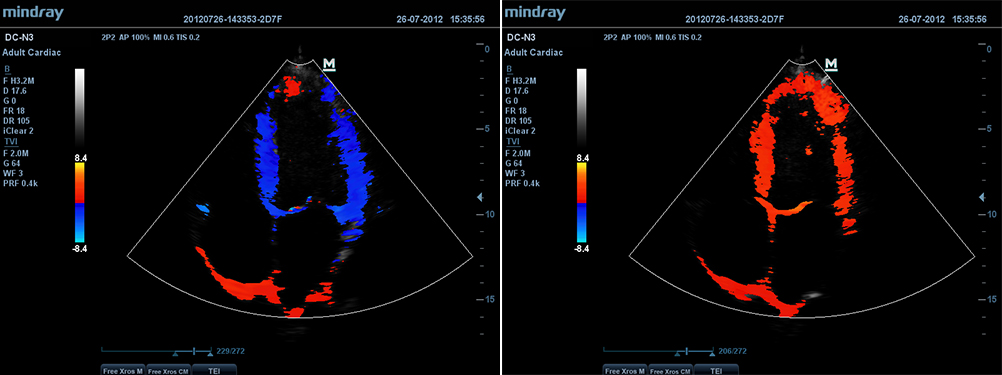

–í–∏–∑—É–∞–ª–∏–∑–∞—Ü–∏—è –≤ —Ä–µ–∂–∏–º–µ —Ç–∫–∞–Ω–µ–≤–æ–π –¥–æ–ø–ø–ª–µ—Ä–æ–≥—Ä–∞—Ñ–∏–∏ (TDI)

–ò—Å—Å–ª–µ–¥–æ–≤–∞–Ω–∏–µ –≤ —Ä–µ–∂–∏–º–µ —Ç–∫–∞–Ω–µ–≤–æ–π –¥–æ–ø–ø–ª–µ—Ä–æ–≥—Ä–∞—Ñ–∏–∏ –ø–æ–∑–≤–æ–ª—è–µ—Ç –æ–ø—Ä–µ–¥–µ–ª—è—Ç—å –∫–æ–ª–∏—á–µ—Å—Ç–≤–µ–Ω–Ω—ã–µ –ø–æ–∫–∞–∑–∞—Ç–µ–ª–∏ –¥–≤–∏–∂–µ–Ω–∏—è –∏ —Ñ—É–Ω–∫—Ü–∏–æ–Ω–∏—Ä–æ–≤–∞–Ω–∏—è —Å–µ—Ä–¥–µ—á–Ω–æ–π –º—ã—à—Ü—ã, –ø—Ä–µ–¥–æ—Å—Ç–∞–≤–ª—è–µ—Ç –ø–æ–ª–Ω—ã–π —Å–ø–µ–∫—Ç—Ä —Ä–µ–∂–∏–º–æ–≤ —Ç–∫–∞–Ω–µ–≤–æ–≥–æ –¥–æ–ø–ø–ª–µ—Ä–∞ –¥–ª—è —É–º–µ–Ω—å—à–µ–Ω–∏—è –≤—Ä–µ–º–µ–Ω–∏ –∏ –ø–æ–≤—ã—à–µ–Ω–∏—è —Ç–æ—á–Ω–æ—Å—Ç–∏ —É–ª—å—Ç—Ä–∞–∑–≤—É–∫–æ–≤–æ–π –¥–∏–∞–≥–Ω–æ—Å—Ç–∏–∫–∏.